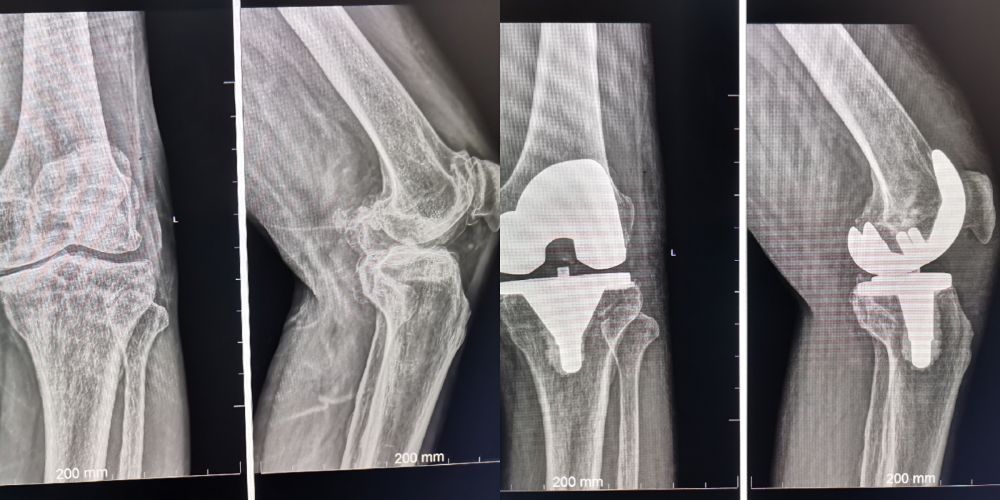

王东方    骨科二病区

副主任医师,原解放军*五一医院骨科主任。擅长髋、膝、肩关节置换及颈、腰椎间盘突出的手术治疗,尤其腰间盘突出微创治疗后创伤小、复发率低。微创治疗各种创伤骨折愈合率高,对颈肩腰腿痛及各种疼痛性疾病有独特的微创治疗手段。

膝关节置换

图片